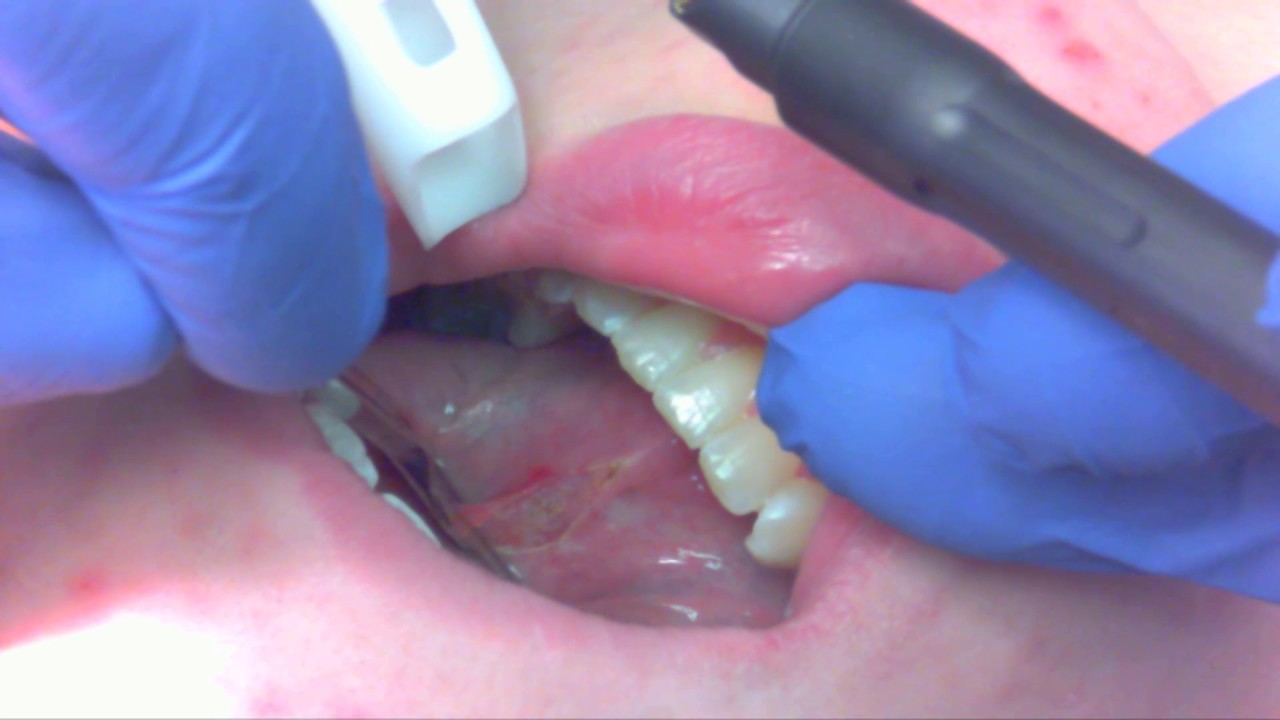

Tongue Tie Release Adults Near Me . Jordan is one of six. With over 20 years of experience in dentistry and surgery, i have developed a gentle and effective approach to treating lip and tongue ties in. The procedure is a relatively fast, often taking less than 10 seconds of laser time to release a tongue or lip tie. Revising a lip tie or tongue tie is a. An adult tongue and upper lip tie surgery is a relatively quick, outpatient procedure typically performed with local anesthesia. If you are looking for providers in your area here are some resources and databases that i found helpful as i was beginning my search: Adequate tongue movement is necessary for swallowing and speech. When tongue movement is restricted, evaluation by an ent (ear, nose,. The procedure may be performed as early as a couple of days after birth and can be.

Adequate tongue movement is necessary for swallowing and speech. Revising a lip tie or tongue tie is a. An adult tongue and upper lip tie surgery is a relatively quick, outpatient procedure typically performed with local anesthesia. If you are looking for providers in your area here are some resources and databases that i found helpful as i was beginning my search: The procedure is a relatively fast, often taking less than 10 seconds of laser time to release a tongue or lip tie. The procedure may be performed as early as a couple of days after birth and can be. Jordan is one of six. With over 20 years of experience in dentistry and surgery, i have developed a gentle and effective approach to treating lip and tongue ties in. When tongue movement is restricted, evaluation by an ent (ear, nose,.